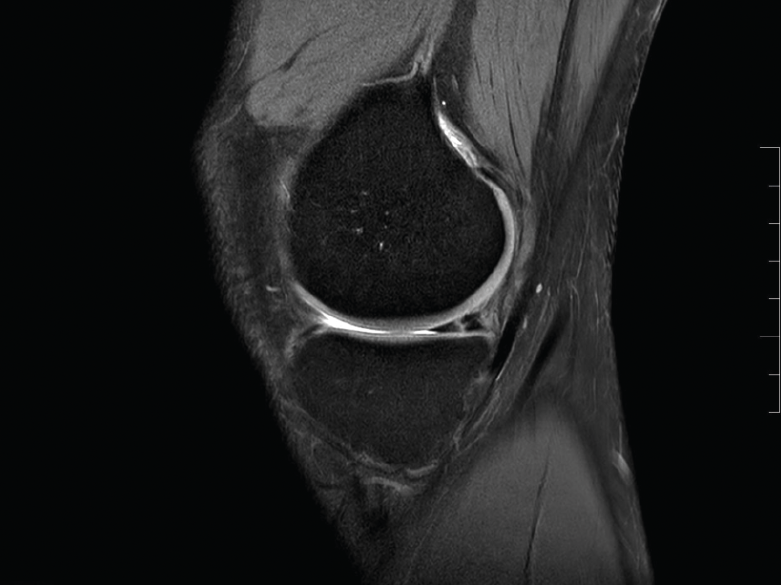

Figura 2. Imagen de rotura vertical en el cuerno posterior del menisco interno.

El tratamiento artroscópico de las lesiones meniscales está indicado en aquellas lesiones que produzcan bloqueo articular, pacientes sintomáticos que no mejoren con tratamiento conservador o aquellos en quienes se vea afectado su nivel deportivo o laboral (Figuras 1 y 2).